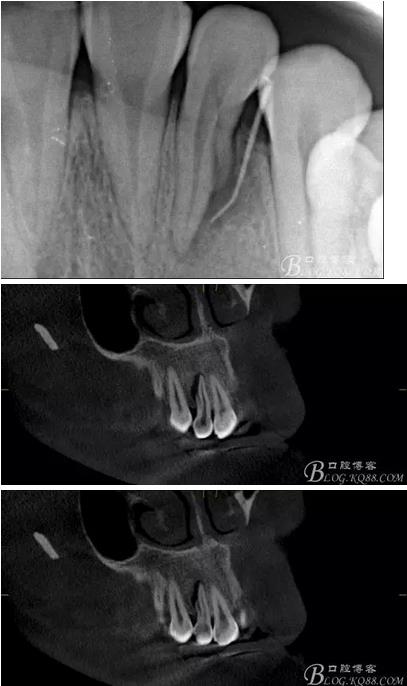

(1) 檢查:12唇側(cè)牙齦可見竇道,牙體顏色較鄰牙暗,無光澤,形態(tài)完整無缺損,唇側(cè)及近遠中向未提及牙周袋。腭側(cè)齦緣輕度紅腫,舌側(cè)窩可探及裂溝,可見浸墨狀痕跡,沿裂溝舌側(cè)探診牙周袋深大于11mm,除患牙外全口牙周狀況良好,為探及牙周袋,牙齦色粉紅。邊緣菲薄,質(zhì)地堅韌。12冷熱診無反應,叩診(+-),無明顯松動,無咬合創(chuàng)傷。12根尖x線片示,根管中三分之一中可見一斜向線樣透射影像根尖區(qū)及遠中根三分之一可見低密度透射暗影,錐形束CT示12根尖區(qū)唇腭向骨吸收已穿通,根面溝達根中三分之一卷曲分出另一牙根,再未見其他明顯的根管系統(tǒng)。